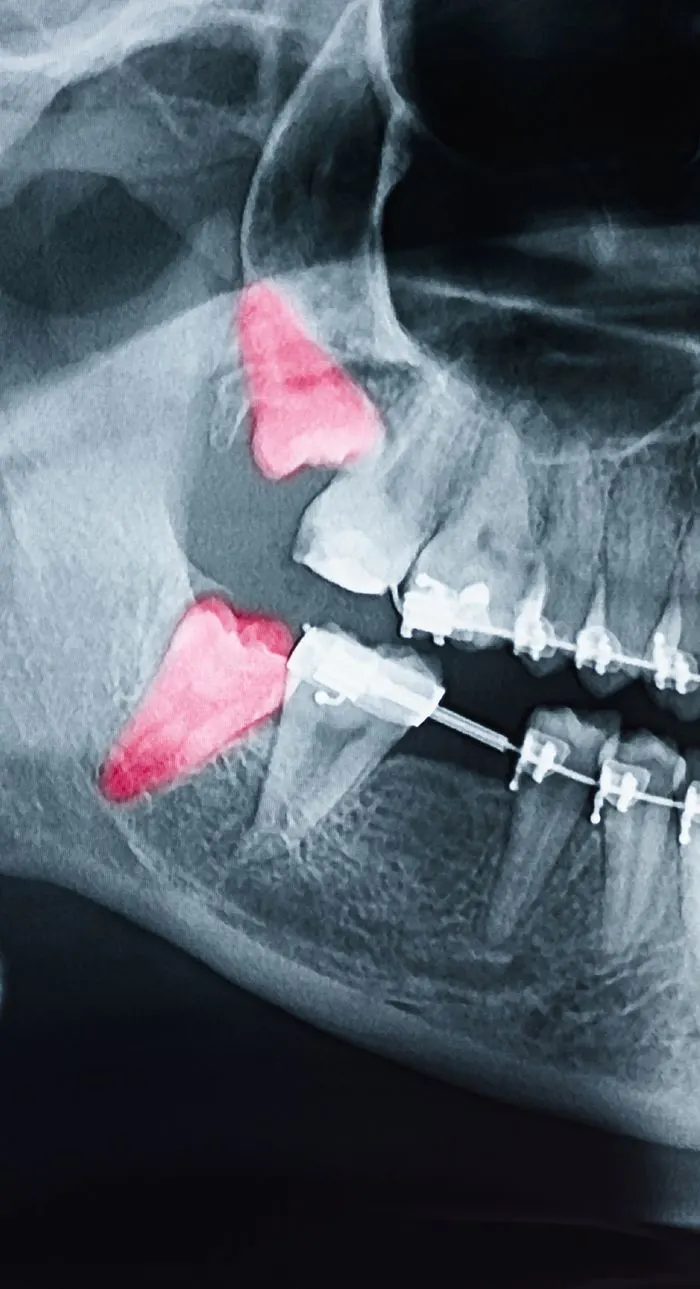

Tooth extractions are typically recommended when a tooth is beyond repair due to severe decay, advanced gum disease, trauma, or infection. Sometimes, a tooth may need to be removed to make room for orthodontic treatment or to prepare for a dental implant or denture.

Wisdom teeth are often extracted if they’re impacted, causing pain, or crowding surrounding teeth. Your dentist will always explore all options before recommending removal, but sometimes extraction is the best way to protect your long-term oral health.